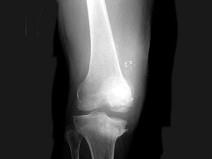

问题 男,67岁,脊髓痨患者,右下肢麻木,右膝关节肿胀,结合图像,最可能的诊断是?(?)

选项 A.创伤性关节炎 B.退行性骨关节病 C.神经性关节病 D.风湿性关节炎 E.痛风

答案 C